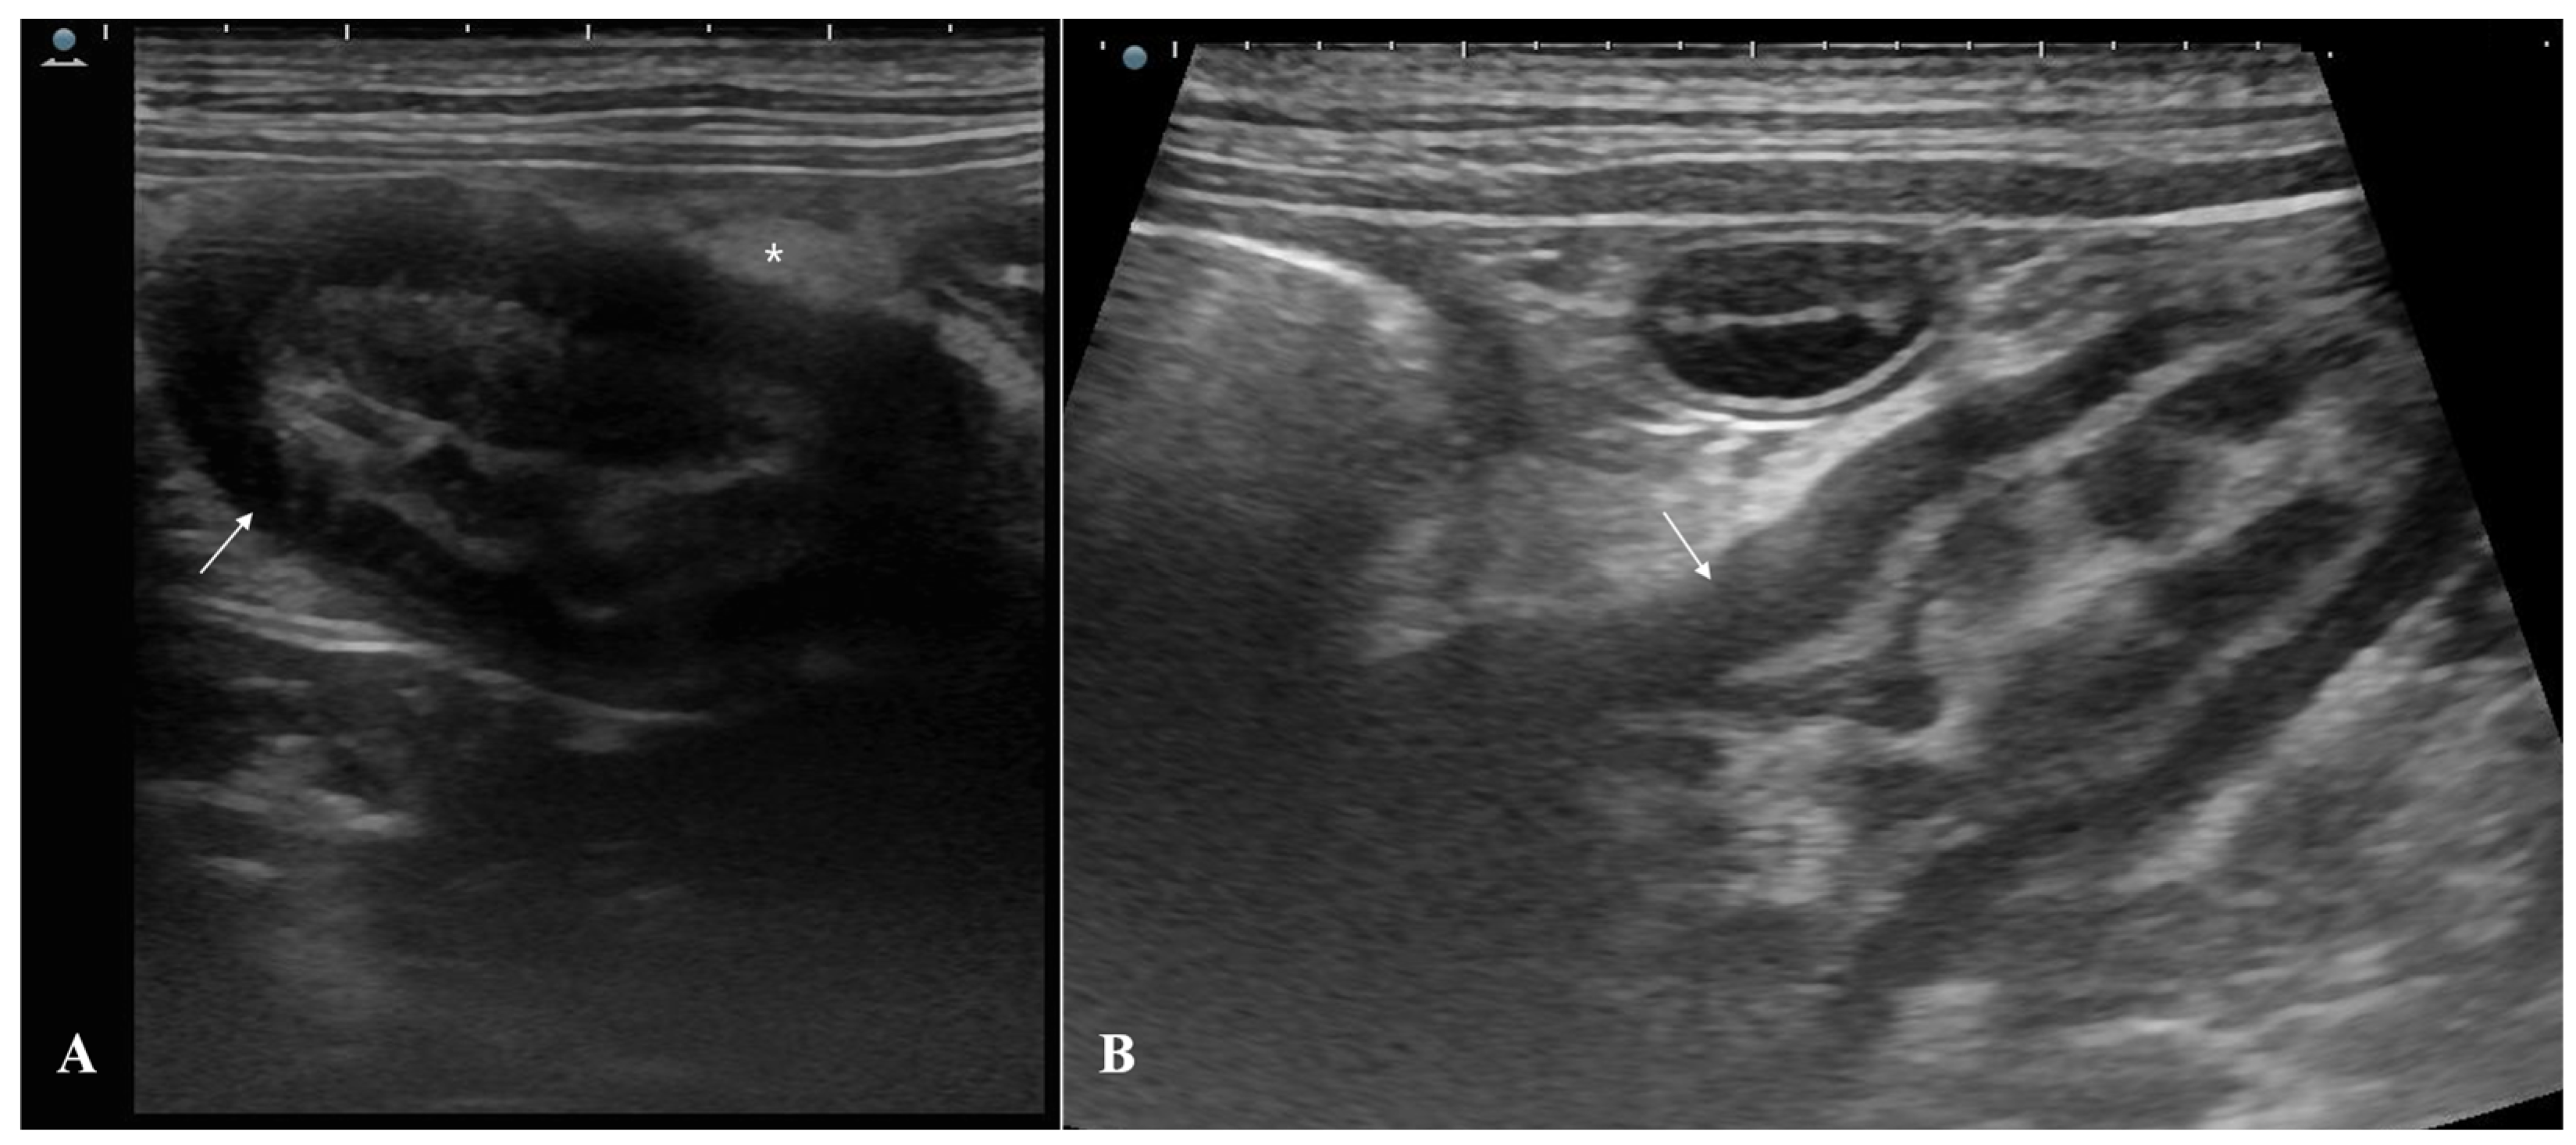

2. Case Description